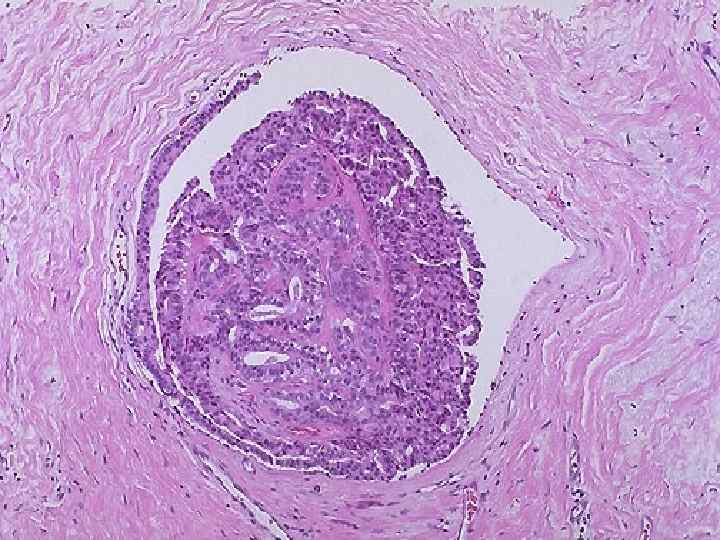

Рак молочной железы Гистологические формы 1. Неинфильтрируюший рак n Внутрипротоковый n Внутридольковый 2. Инфильтрирующий рак 3. Болезнь Педжета